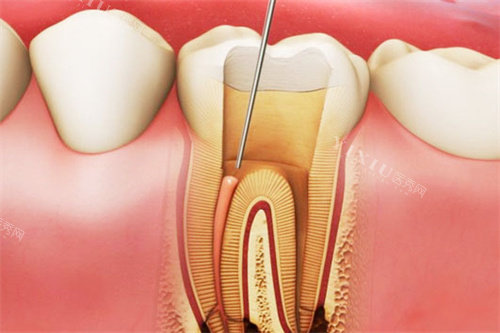

终于轮到我看牙,给我接诊的是张医生,戴着口罩都能感觉到她特别亲切。她先仔细询问了我的症状,然后用仪器检查牙齿,一边检查还一边耐心跟我解释:“你这颗牙龋坏有点深了,得尽快补,不然伤到牙神经就麻烦了。” 接着给我看了补牙的材料,详细介绍了每种材料的优缺点和价格,完全没有强制推销的感觉,我选了性价比比较高的树脂材料。

补牙过程比我想象中轻松很多。张医生动作特别轻柔,打麻药的时候提前提醒我会有点胀胀的感觉,让我别紧张。麻醉起效后,她开始用工具清理龋坏的部分,虽然能听到 “嗡嗡” 的声音,但一点都不疼。清理完后,张医生反复确认牙齿的情况,还拿镜子给我看,让我清楚了解牙齿的状态。填充材料时,她特别细心,一点点调整材料的形状和高度,还让我反复咬合,确保补牙后的牙齿使用起来舒适自然。